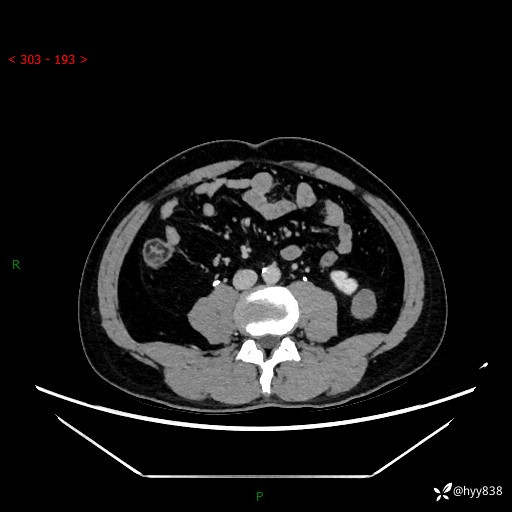

中年男性,左侧腰背部间断性胀痛不适。第一眼“乳头或囊肿”,有无意外---(有结果)

【患者信息】:41岁/男

【主诉】:左侧腰背部间断性胀痛不适1周

【现病史及既往史】:患者1周前无明显诱因出现左侧腰部疼痛,呈间断性胀痛,休息后可缓解,无放射痛,偶可见肉眼血尿,无血块,无尿频尿急尿痛,无夜尿增多,无畏寒发热、咳嗽咳痰等症状。于我院查双肾CT示:左肾占位性病变,左肾下极囊性病变,左肾轻度积水,胆囊多发结石。今为求进一步诊治来我院,门诊以“左肾占位性病变”收治入院。 起病以来,患者精神佳,饮食、睡眠良好,大便正常,小便如上诉,体力体重无明显变化。

【检查】:肾脏CT平扫+增强